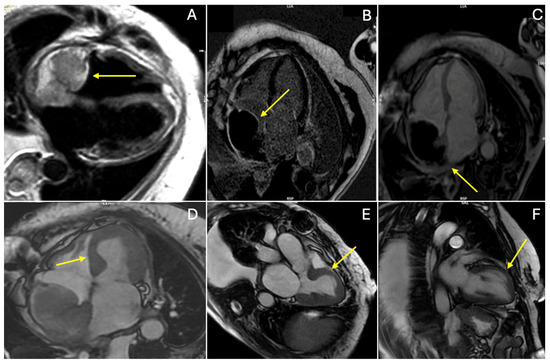

3. Discussion